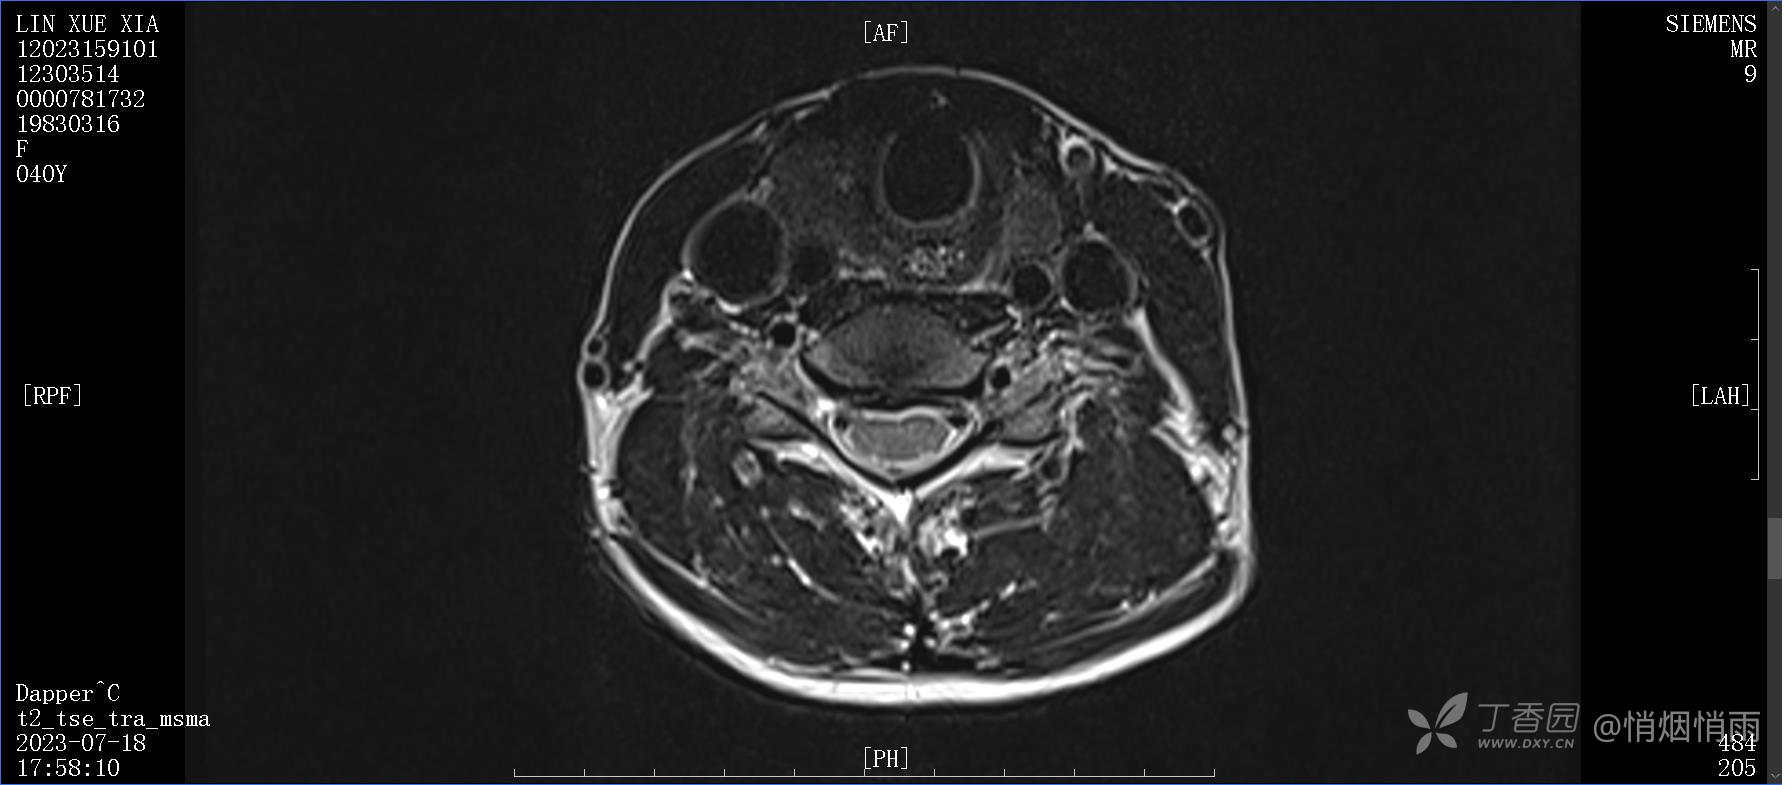

查体:右肩关节局部轻度肿胀,肩胛区压痛明显,痛处不固定,肩关节痛性活动受限,jobe test(+),lift -off test(+),中指、环指感觉较余指减退,余肢端感觉及血运情况可。

目前的诊断,暂时依据辅助检查诊为肩袖损伤,但是患者疼痛的性质和特点,却不是单纯的肩袖损伤所致。考虑过胸廓出口综合征,但是该疾病会出现肩胛区的疼痛吗?(由于考虑到费用的问题,没再进行下一步的检查)带状疱疹会有如此的症状吗?